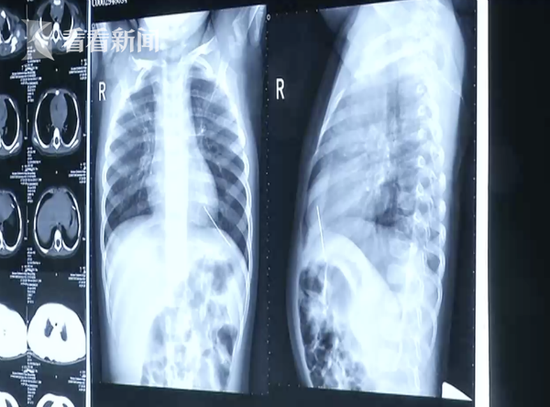

The needle, measuring 2mm in diameter, was found in the child's left heart ventricle.

According to Taiwan's China Times, doctors took two X-rays and found a foreign object in the girl's chest cavity.

Through further checks, it was determined that the object was located in Chenchen's left heart ventricle.

That night, Chenchen went through an emergency operation and the needle, measuring 2mm in diameter, was successfully removed.